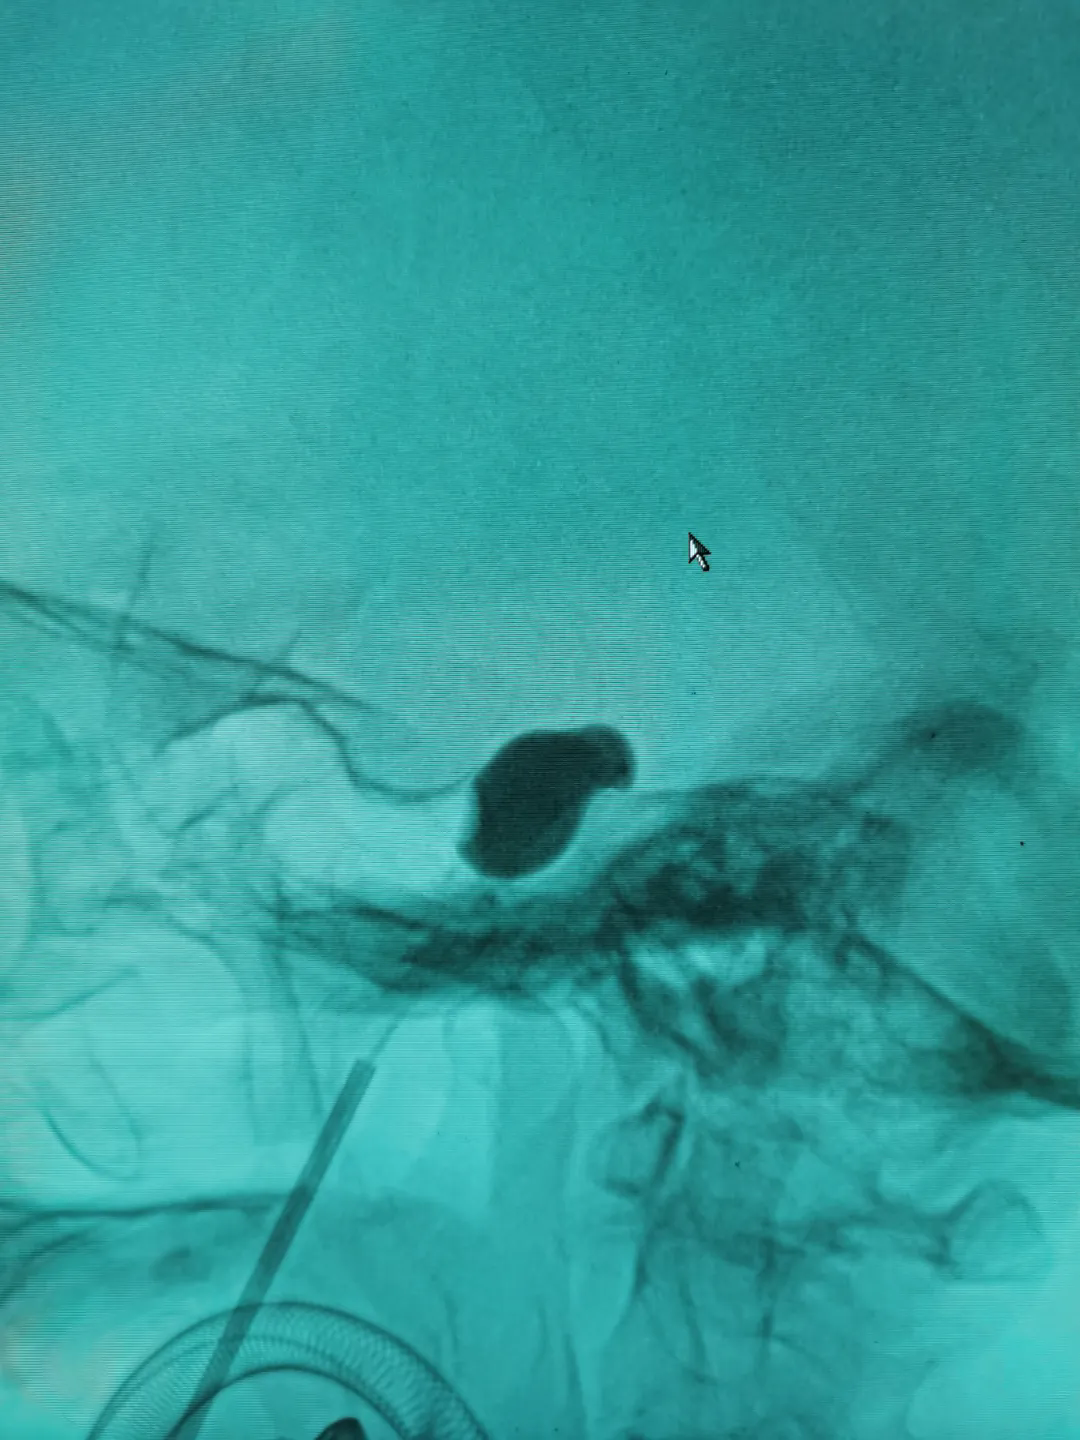

一切準(zhǔn)備就緒,在麻醉科、導(dǎo)管室醫(yī)護(hù)人員的密切配合下,施宏飛主任帶領(lǐng)團(tuán)隊(duì)成員尹志強(qiáng)醫(yī)生在患者面部用穿刺針將球囊導(dǎo)管置入三叉神經(jīng)半月節(jié),再將造影劑注入球囊中,待球囊擴(kuò)張呈“梨形”后,精準(zhǔn)壓迫引起疼痛的神經(jīng),完成后拔出穿刺針及球囊導(dǎo)管,三十分鐘就完成了手術(shù)。